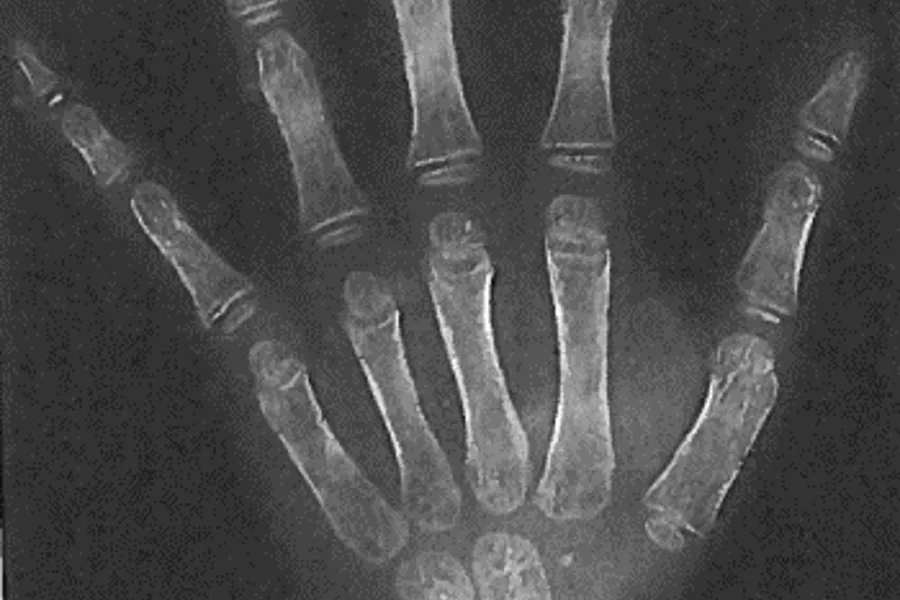

Arbeidet med kunnskapsoppsummeringene på ulike metoder for biologisk aldersfastsetting viste at det var mest vitenskapelig dokumentasjon på metodene som benyttet utvikling av visdomstenner og hånd/håndrot.

I BioAlder er det samlet inn over 24 000 observasjoner av tannstadium og håndskjelett, som deretter ble brukt til å et statistisk prediksjonsverktøy for kronologisk alder ved hjelp av biologiske målinger.